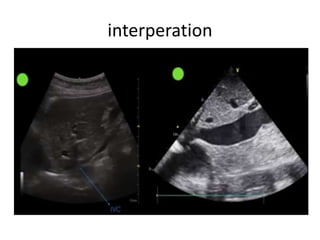

interperation

Can it replace CVP measurement?